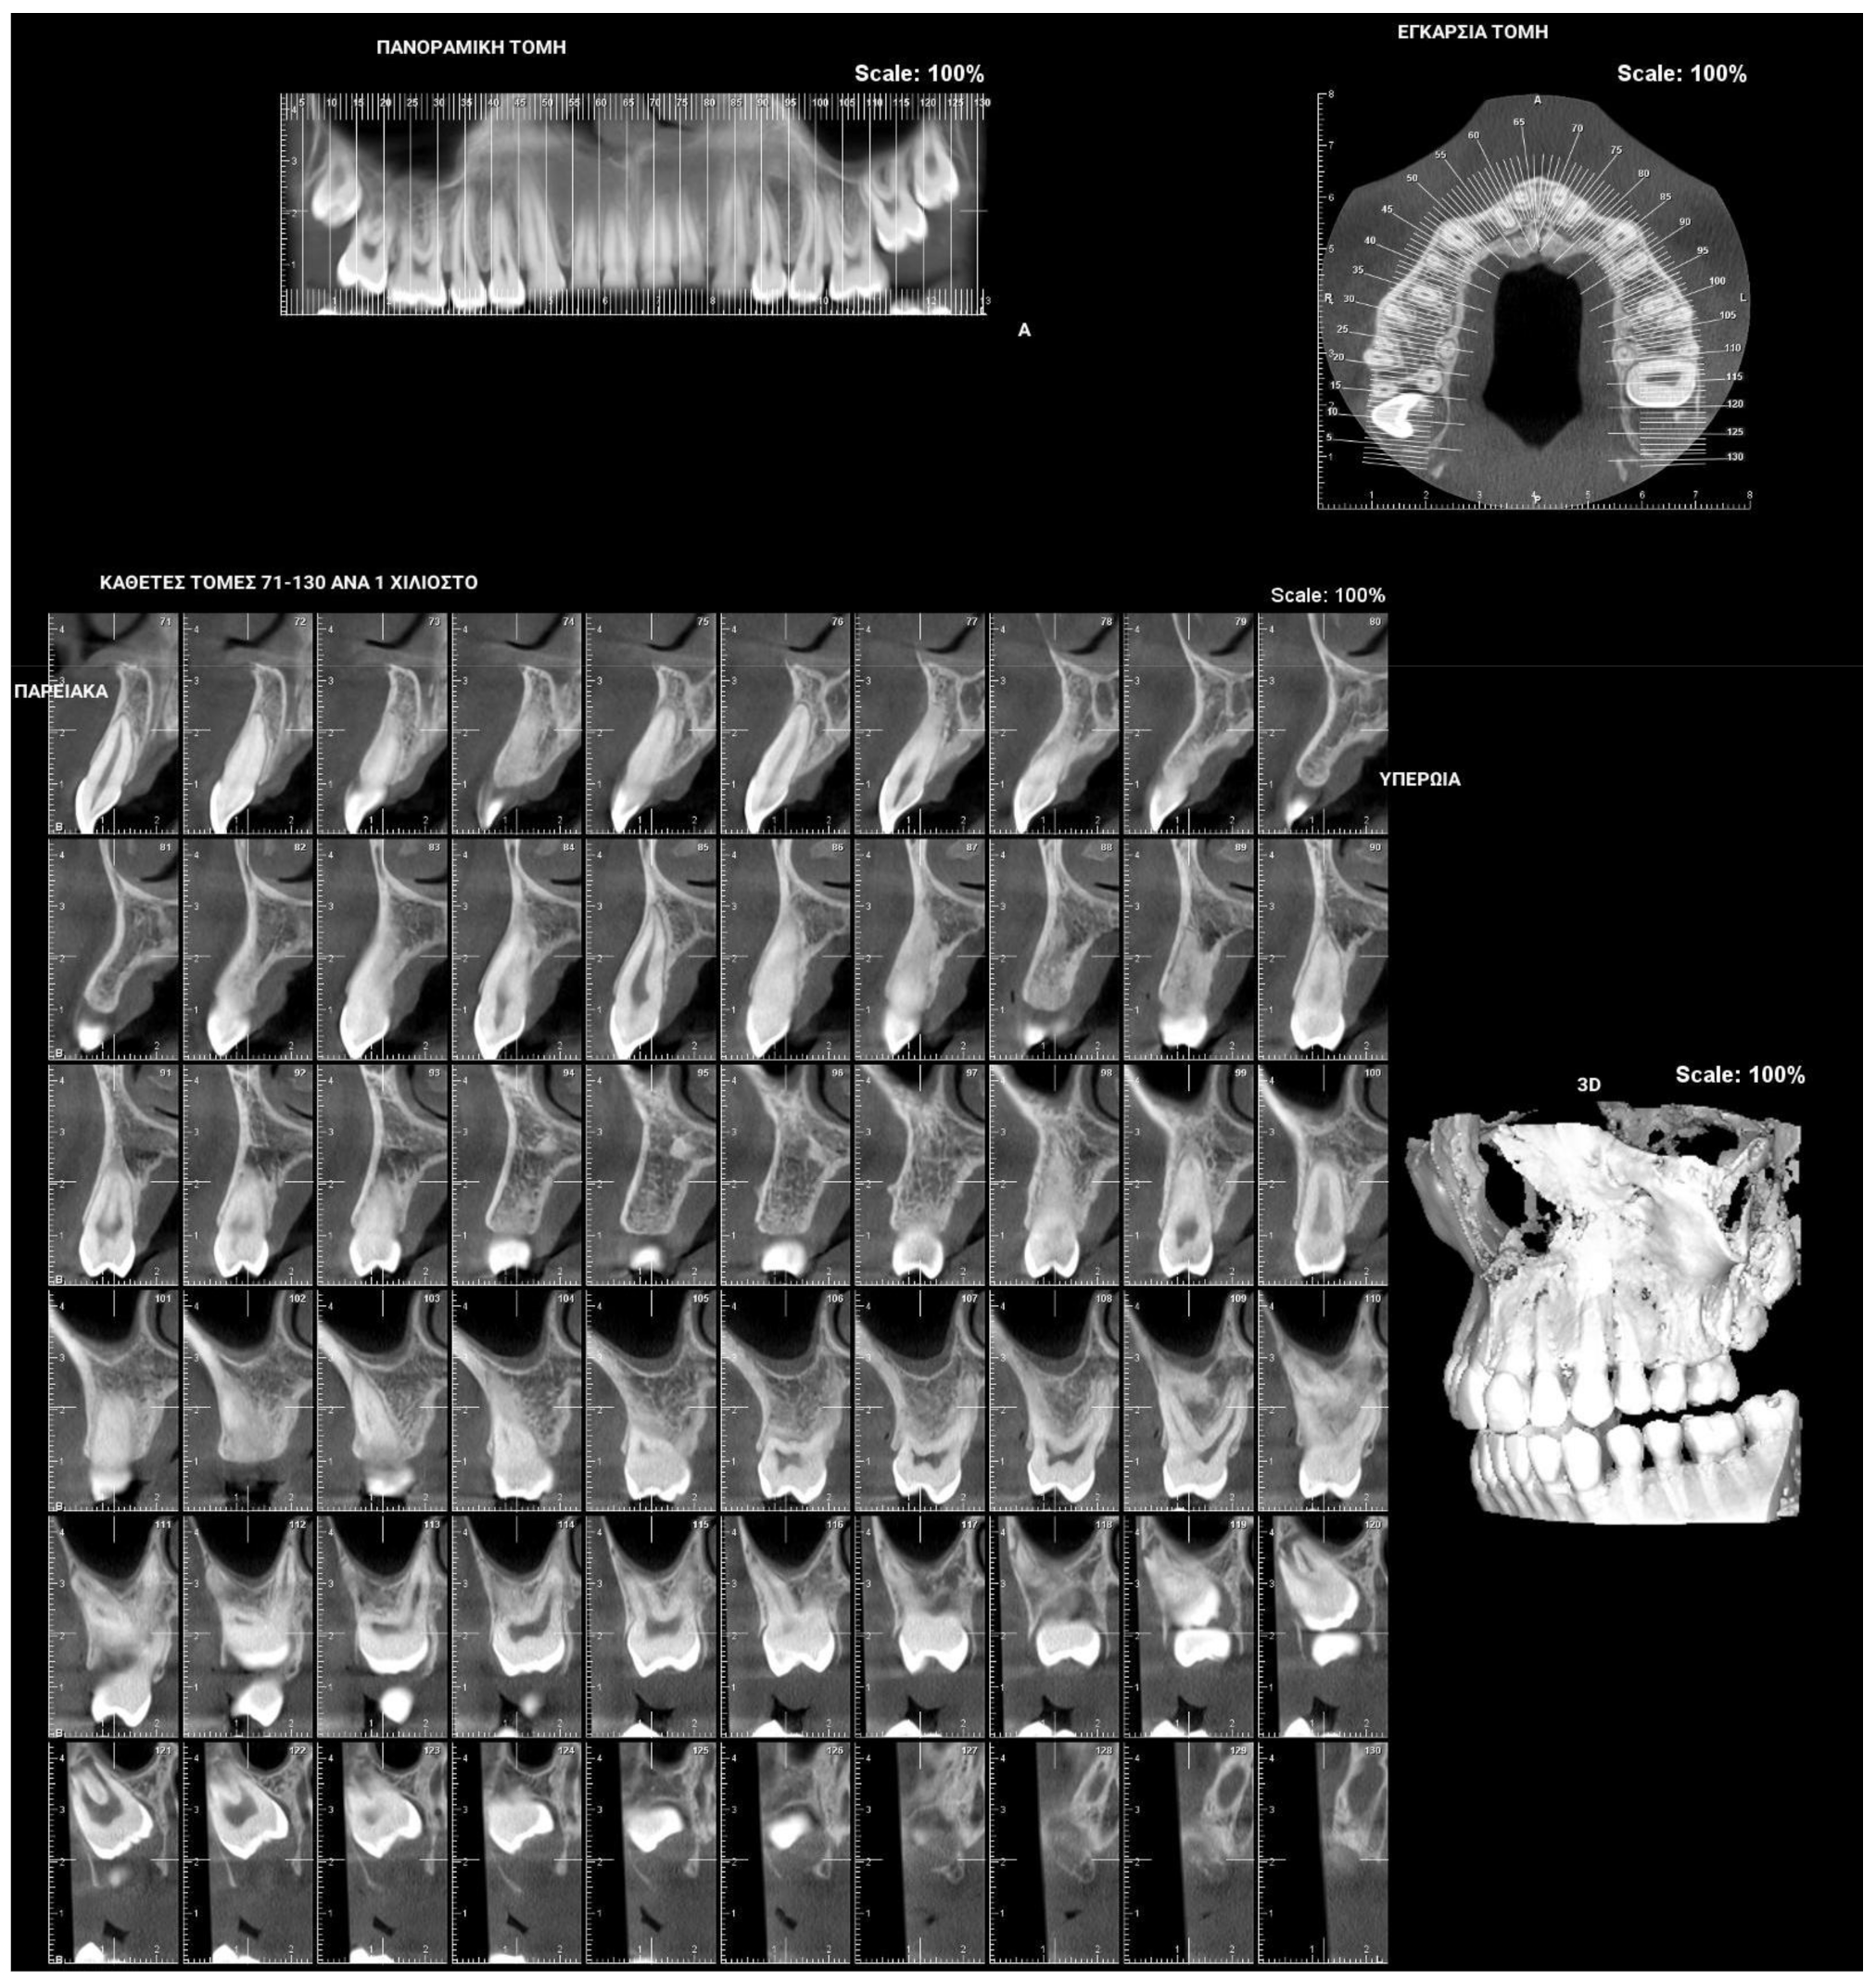

PFE attributes combine elements that resemble both primary and secondary retention (Figure 4). The diagnosis of PFE is impeded to a great extent by the complexity of this clinical picture (Figure 5 and Figure 6). It appears that this clinical condition has two different mechanisms or two different aspects of the same mechanism since the tooth may erupt in its initial position and thereafter stop its further eruption (a clinical condition known as secondary retention) [7,8,14], or the tooth may not be able to erupt at all [11]. In this context, a definitive diagnosis of PFE cannot easily be decided, as it is possible that PFE presents two separate mechanisms [11] or two independent manifestations of the same mechanism. Only if we were to examine an environment where genetic, pathological, and environmental factors—all factors potentially responsible for the discontinuation of the tooth’s eruption—are absent would a PFE diagnosis through a retrospective examination be possible.

Figure 4.

Patient’s orthopantomography presenting Primary Failure of Eruption in all four dental quadrants.

Treatment of PFE is hindered by the fact that its diagnosis is difficult. Indeed, its diagnosis can only be made possible after the potential etiologic factors have been ruled out and the attempt to apply orthodontic forces on a tooth has been unsuccessful, hence resulting in ankylosis [7]. In this case, the PFE diagnosis is corroborated by X-rays in which the periodontal ligament is absent; a lack of normal tooth mobility; and a solid, sharp sound of the tooth [22]. However, the mere absence of the periodontal ligament could wrongly lead to the diagnosis of ankylosis; in such cases, the detection of the mutated gene PTH1R may result in the right final diagnosis [2].

Figure 5 and Figure 6 present a PFE case of a 17-year-old female patient referred to the Orthodontic Clinic of the Dental School of the National and Kapodistrian University of Athens, Greece. Clinical examination showed a posterior open bite on the right segment, as well as infraoccluded left upper and lower first molars. The patient’s orthopantomography shows no visible PDL of the right upper and lower first molars or the teeth distally related to them.